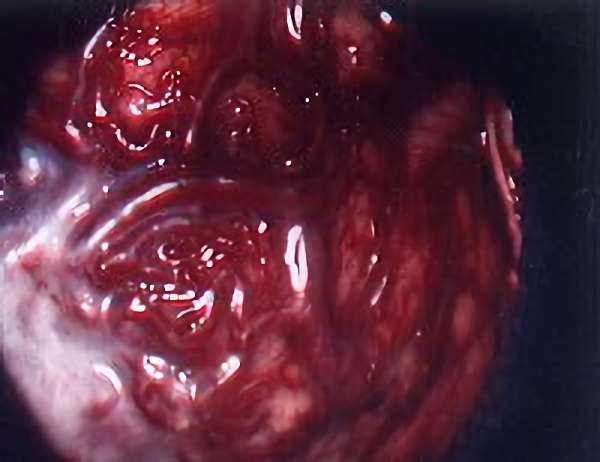

脳血管撮影

手術前

手術後

手術中

モニタリング

手術写真

手術の結果